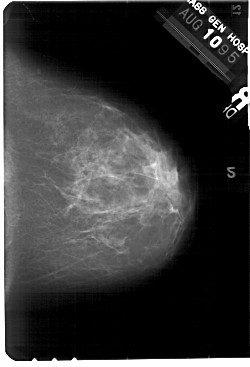

A_1445_1.LEFT_MLO

LEFT_MLO LINES 5491 PIXELS_PER_LINE 3916 BITS_PER_PIXEL 12 RESOLUTION 43.5 OVERLAY

FILE: A_1445_1.LEFT_MLO.OVERLAY

TOTAL_ABNORMALITIES 1

ABNORMALITY 1

LESION_TYPE MASS SHAPE ROUND MARGINS OBSCURED

ASSESSMENT 3

SUBTLETY 2

PATHOLOGY BENIGN

TOTAL_OUTLINES 1

BOUNDARY